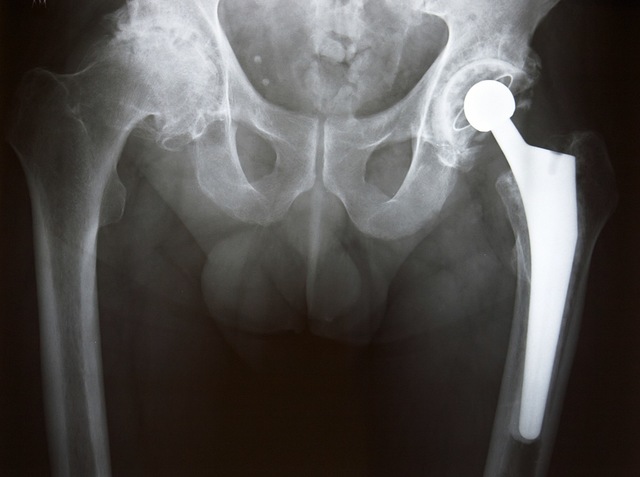

Had my hip replaced a year ago.

I have been miserable with hip pain for years now. Scheduled hip replaced for now-abouts, before I went in I'd made 6 sets with #5 Bridgere and Sterling 600's. Huge baits and scent pads, So far we(my wife) are up to 5 Wolverines and maybe more!!

Sit in on a chair and stretch out you leg. Have someone take ahold of your foot by the heal and toes, now give a twist left or right. If this sends you thru the roof the you need a new hip. I had both done in 2012, the first one went well but the second not as good. Both are great now. Since 2012 I had back surgery and last March a stent put in. Mayo Clinic has been great. I called Mayo Clinic on March 17 and told my nurse about my chest pains going down my arm, his commit was you get here tomorrow. I got there at 7:45 AM and I was in my room by 10:45 all done with a stent. Mayo new about my chest pains from an earlier visit so I was not a surprise.